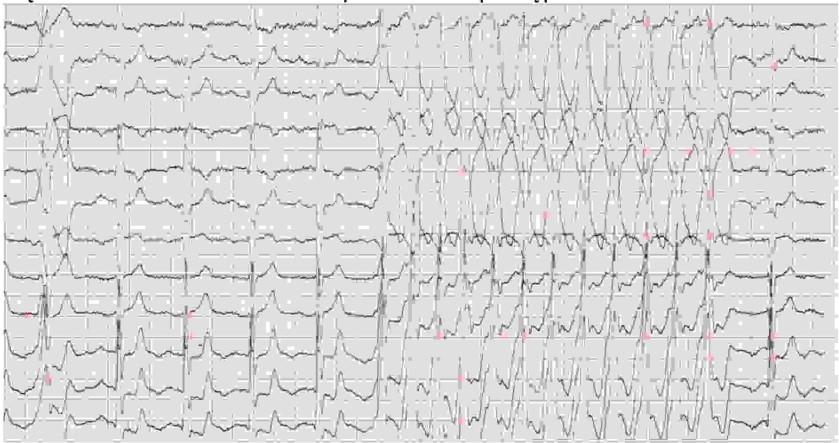

70-letnia kobieta po zawale serca wezwała ZRM z powodu zasłabnięcia. ZRM stwierdził RR 110/70 mmHg, puls 150/min, saturacja 93%. Na podstawie przedstawionego zapisu EKG wskaż prawidłowe postępowanie:

Pytanie 82